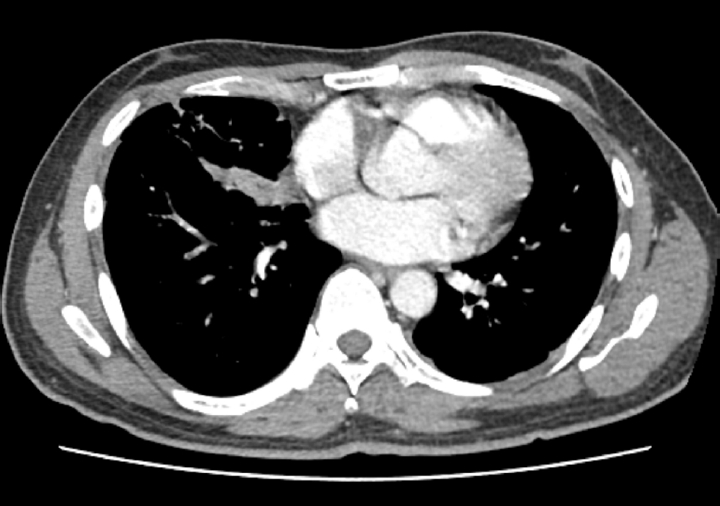

Empirical intravenous antibiotic therapy with piperacillin/tazobactam and levofloxacin was administered. On the second day of admission, the patient developed hemoptysis for which intravenous tranexamic acid was administered for 5 days, followed by oral maintenance. Clinical improvement was not achieved following a 7-day course of intravenous antibiotics, with the clinical course marked by unresolved febrile episodes and persistent leukocytosis. Furthermore, a follow-up chest CT on hospital day 7 revealed aggravation of the internal cavitations and abscess formation within the consolidative lesions of the right middle lobe and both lower lobes (Fig. 2). The failure of conservative management to arrest the necrotizing process, combined with the high risk of secondary sepsis from the poorly drained, inspissated purulent material, prompted the decision to escalate to video-assisted thoracoscopic surgery (VATS) for definitive source control and debridement. Intraoperative examination revealed dense pleural adhesions and extensive necrosis of the lung parenchyma. Thick, yellowish, and inspissated purulent material was drained from the abscess cavities located in the right middle and left lower lobes (Fig. 3). Given the deep and multiloculated nature of the abscesses, wide unroofing was performed via wedge resection using an endoscopic stapler and ultrasonic shear to ensure adequate drainage. Subsequently, thorough decortication and irrigation of the thoracic cavity were performed. A closed thoracostomy was performed with chest tube and Hemovac placement. Histopathological examination of the lung tissue revealed acute fibrinous and organizing pneumonia, consistent with chemical exposure.

Fig. 2.

Chest computed tomography on day 7 revealing multiloculated abscesses involving right middle and left lower lobes.

Fig. 2. Chest computed tomography on day 7 revealing multiloculated abscesses involving right middle and left lower lobes.